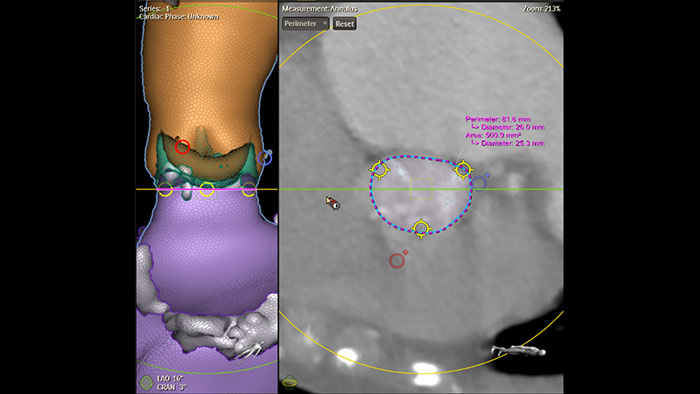

Dimensionamiento de la TAVR totalmente automatizado con HeartNavigator

Evaluación automatizada de la ruta de acceso Intellispace Cardiovascular